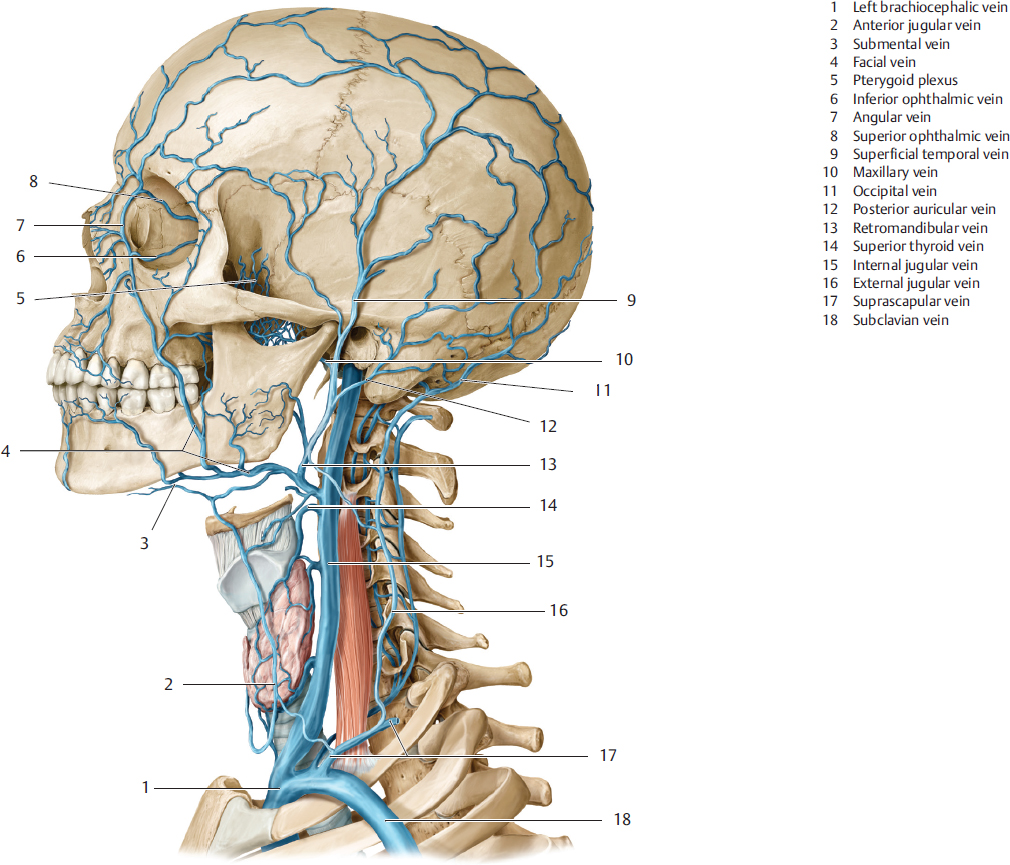

Анатомия внутренней яремной вены: КТ изображения